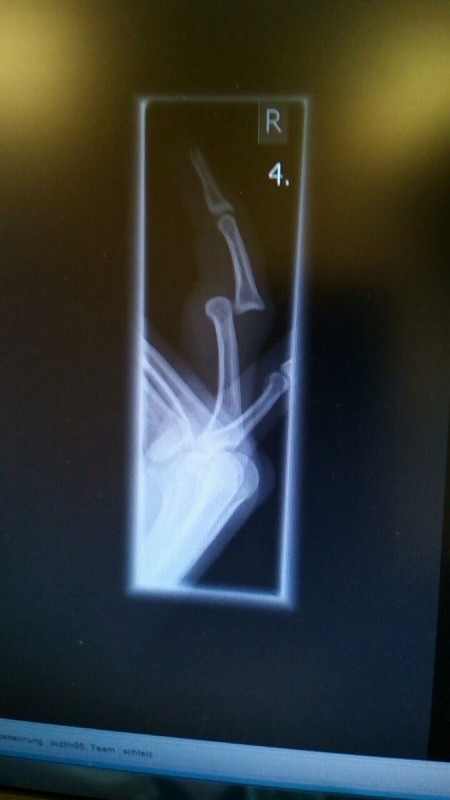

(Wie auf dem Bild zu sehen, verletzte sich unser Torhüter W. Blöthner im Training schwerer. Zusätzlich zur hier sichtbaren Fehlstellung des Fingers kommen weitere Prellungen und Ergüsse im Gesichtsbereich.)

Dass es dabei auch manchmal etwas härter zugeht, musste unser Nachwuchstorhüter W. Blöthner am eigenen Leib erfahren. Er prallte im Dienstagstraining unglücklich mit A. Pohl zusammen und zog sich zusätzlich zum nun stark zugeschwollenen Augen- u. Nasenbereich eine Verletzung des für den Torwart so wichtigen Fingerapparates zu.